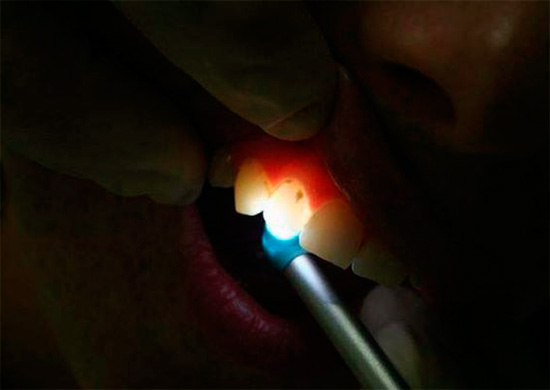

Прихований карієс - де може ховатися уражена порожнина і як її виявити?

Існують наступні методи діагностики

Огляд за допомогою дзеркала.